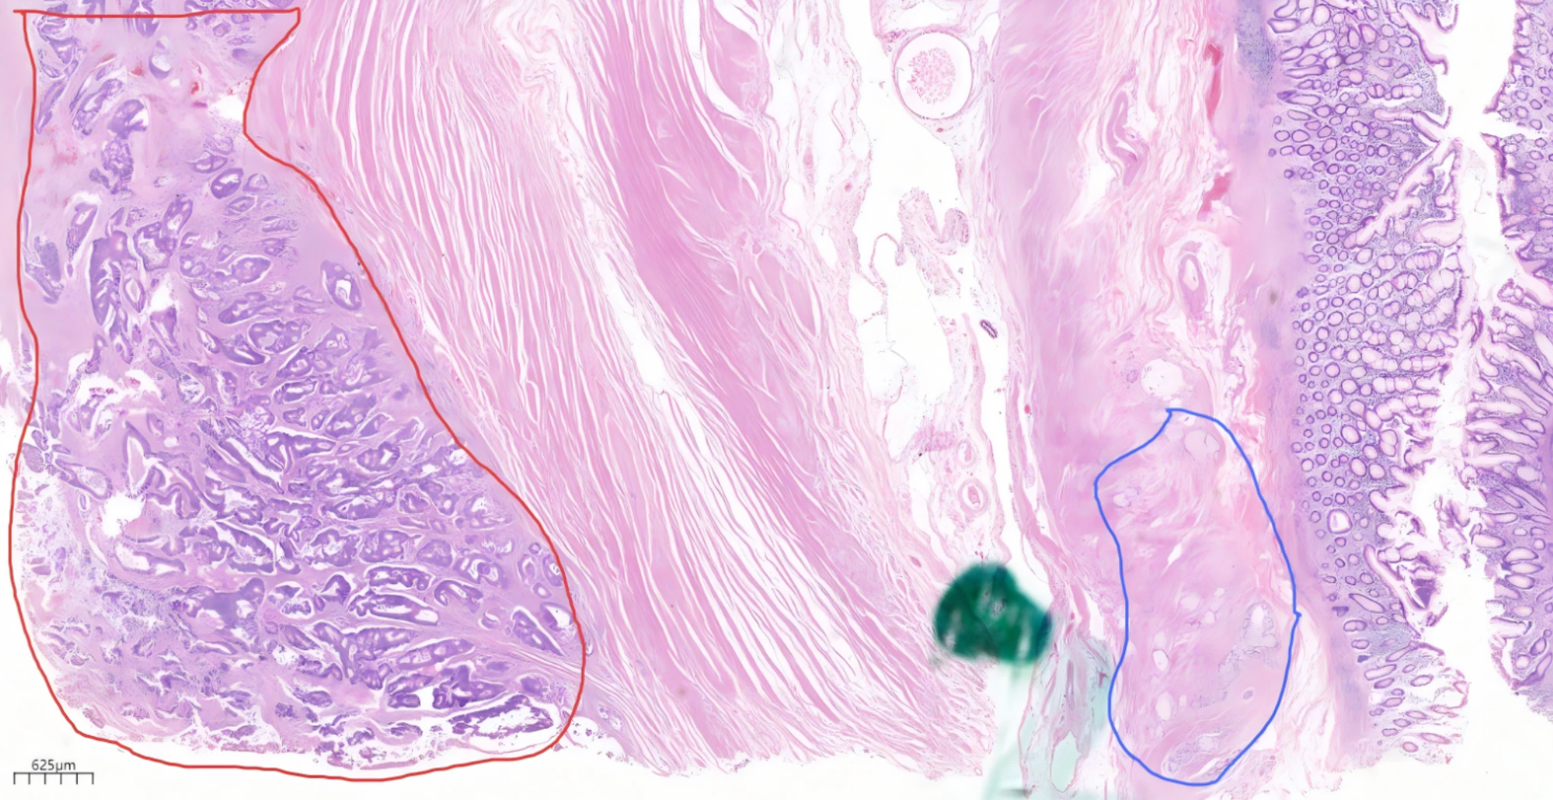

基于术中探查和术后病理,患者最终诊断:原发性盲肠管状腺癌合并阑尾杯状细胞腺癌,盲肠管状腺癌分期为T4aN0M0 II期IIC,阑尾杯状细胞腺癌分期为T4N0M0 II期IIB。

盲肠溃疡肿块内的管状腺癌(左侧红色圆圈内)和阑尾基底部附近盲肠固有肌层之间的杯状细胞癌(右侧蓝色圆圈内)

盲肠管状腺癌